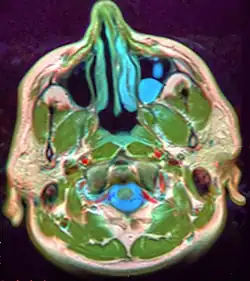

Microscopically, mucoceles appears as granulation tissue surrounding mucin. Since inflammation occurs concurrently, neutrophils and foamy histiocytes usually are present. On a CT scan, a mucocele is fairly homogenous, with an attenuation of about 10-18 Hounsfield units.[5]